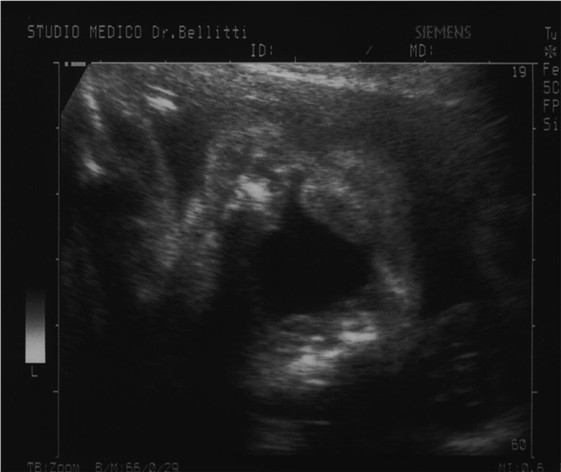

Diagnosi Prenatale - La diagnosi prenatale di Labio-palatoschisi è molto difficile e in alcuni casi impossibile; pertanto talvolta è tardiva (IIIº trimestre) o non viene fatta. La diagnosi consiste nella dimostrazione diretta della fissurazione del labbro. Dopo la diagnosi di labioschisi e la sua definizione (mono- o bi-laterale) si deve tentare di visualizzare il palato, per verificare l’eventuale associazione con la palatoschisi. La diagnosi prenatale di palatoschisi non è agevole, e nei casi in cui non è associata alla labioschisi, spesso sfugge alla diagnosi prenatale. Quando diagnosticata, la labio-palatoschisi non pone grossi problemi di diagnosi differenziale, rispetto ad atre patologie. La Labiopalatoschisi nell’ 80% dei casi non è associata ad altre anomalie, mentre nel 20% dei casi fa parte di sindromi polimalformative (soprattutto del Sistema Nervoso Centrale) o è presente in feti affetti da patologie genetiche (sia geniche che cromosomiche), soprattutto alla Trisomia 18 (Sindrome di Edwards) ed alla Trisomia 13 (Sindrome di Patau).  Pertanto è estremamente importante sia la ricerca di altre malformazioni, sia lo studio del cariotipo nei casi diagnosticati precocemente.